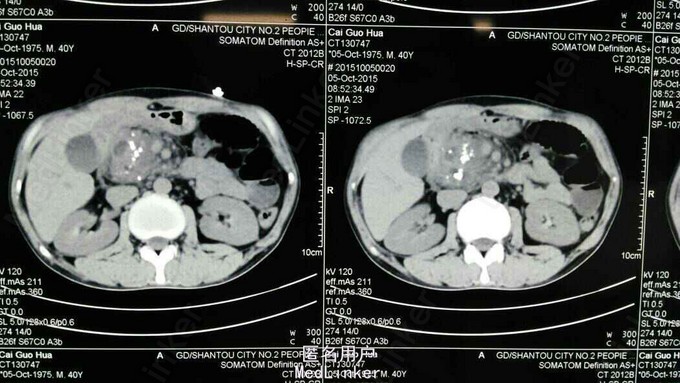

查体:T 36.4℃ P 104次/分 R 20次/分 Bp 109/75mmHg 急性痛苦面容,神志清,精神稍疲,对答切题,查体合作。全身皮肤黏膜无黄染、出血点,全身浅表淋巴结未扪及肿大。睑结膜无苍白,巩膜无黄染,双侧瞳孔等圆等大,直径约2.5mm,对光反射灵敏。颈软,无抵抗,颈静脉无怒张,双肺呼吸音稍粗,未闻及干、湿性啰音,心率104次/分,律齐。上腹肌紧张,腹平,未见肠型及蠕动波,左上腹、中上腹压痛,无反跳痛,肝脾触诊不满意,肝肾区叩痛(-),移动性浊音(-),肠鸣音活跃。辅助诊断:血常规示白细胞 5.9×10^9/L 中性粒细胞比率 61%,血红蛋白 151g/L,血小板341×10^9/L;(10-4)生化示葡萄糖5.14mmol/L,钾4.15mmol/L,钙2.21mmol/L,淀粉酶154U/L,脂肪酶357U/L;血气分析未见异常;腹部彩超示肝无明显占位,胆囊稍大,无结石,胰腺显示不清;腹部平片未见肠梗阻及消化道穿孔征象。入院后查上腹部CT:1.胰头部明显肿胀,呈混杂密度影,考虑炎症性改变并周围渗出,胰头部、胰管近端多发结石或钙化;肿瘤常规:甲胎蛋白 7.9ng/ml,癌胚抗原 1.31ng/ml,CA-199 3.84ng/ml;(10-5)生化:葡萄糖 4.48mmol/l,钙 2.19mmol/l,总胆红素 24.4umol/l,谷丙转氨酶 10U/L,淀粉酶142U/L,脂肪酶168U/L; 上腹部MRI+MRCP示考虑慢性胰腺炎急性发作,胰头部假性囊肿形成,胰头区多发钙化灶,未除外胰头Ca可能,请结合临床